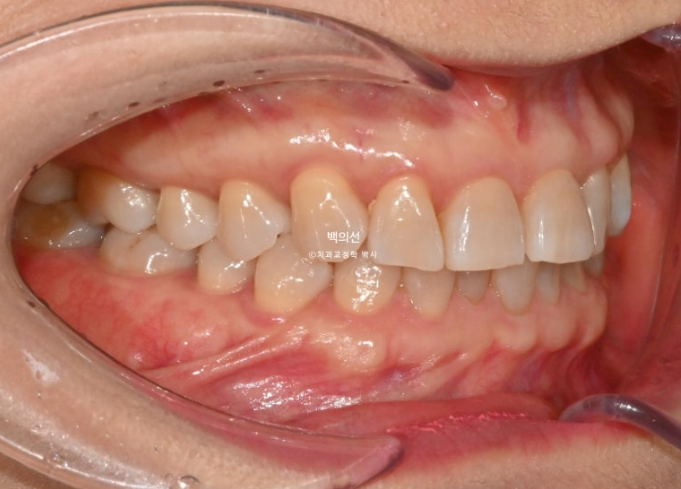

25.02

앞니의 뻗침이 있습니다.

앞니 뿐 아니라 송곳니가 튀어나왔던 부분도 배열이 개선이 되었습니다.